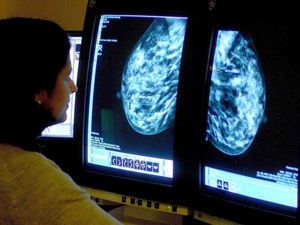

New test could predict breast cancer recurrence

A routine test could soon help doctors predict when and where treated breast cancer is likely to return.

Scientists have found molecular clues in breast tumours that indicate how the disease is likely to progress.